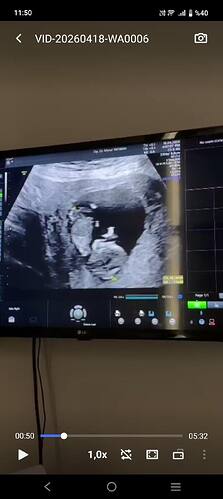

Canım çok net değil ama başka var mı yakin ve net tahmin edecek olursak erkek bebek gibi

Ters duruyor du zaten baş aşağı dı Doktor ne kız dedi ne erkek haftaya konuşuruz dedi kararsız kaldım dedim

Anladım baş aşağı durduğunu orda çıkıntı var o yüzden erkek gibi geldi kordon değil ise